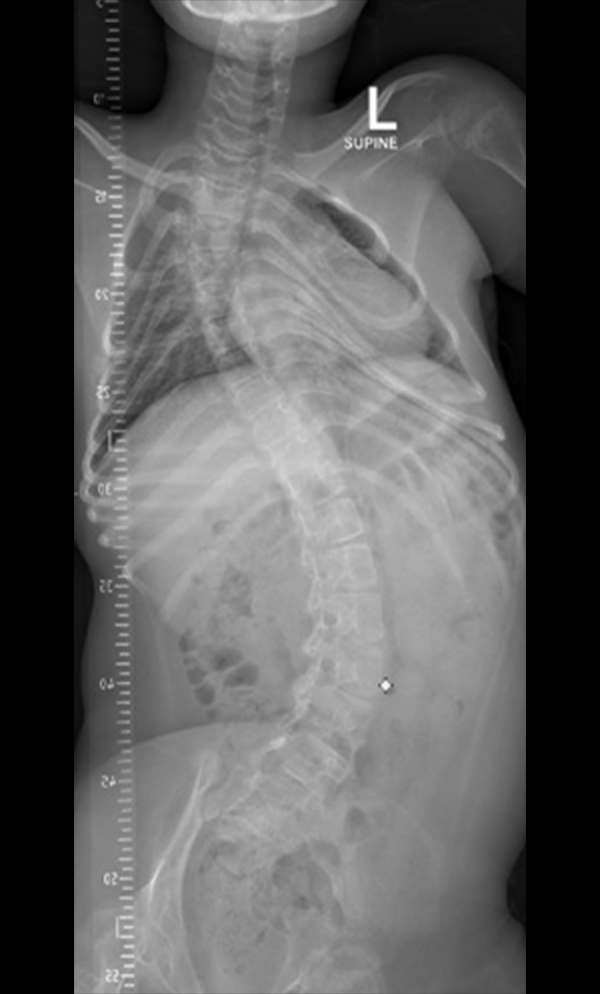

Gallery : Before - After

After

Before